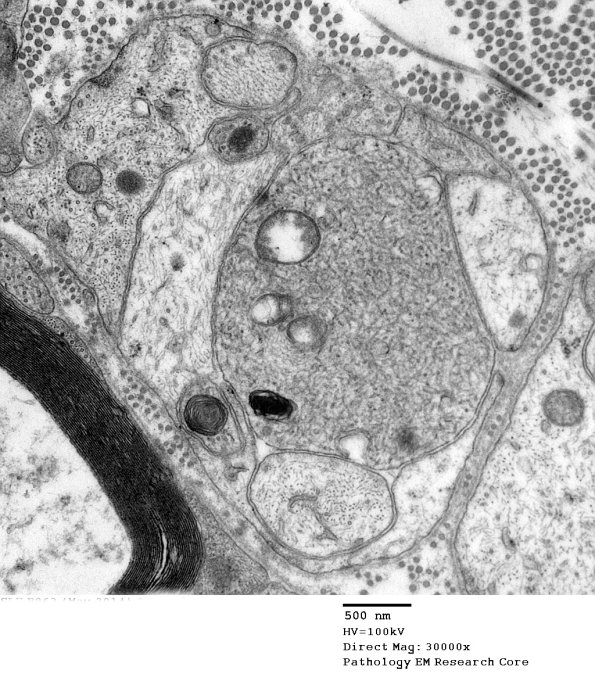

Higher magnification of image 3B10. (electron micrographs)